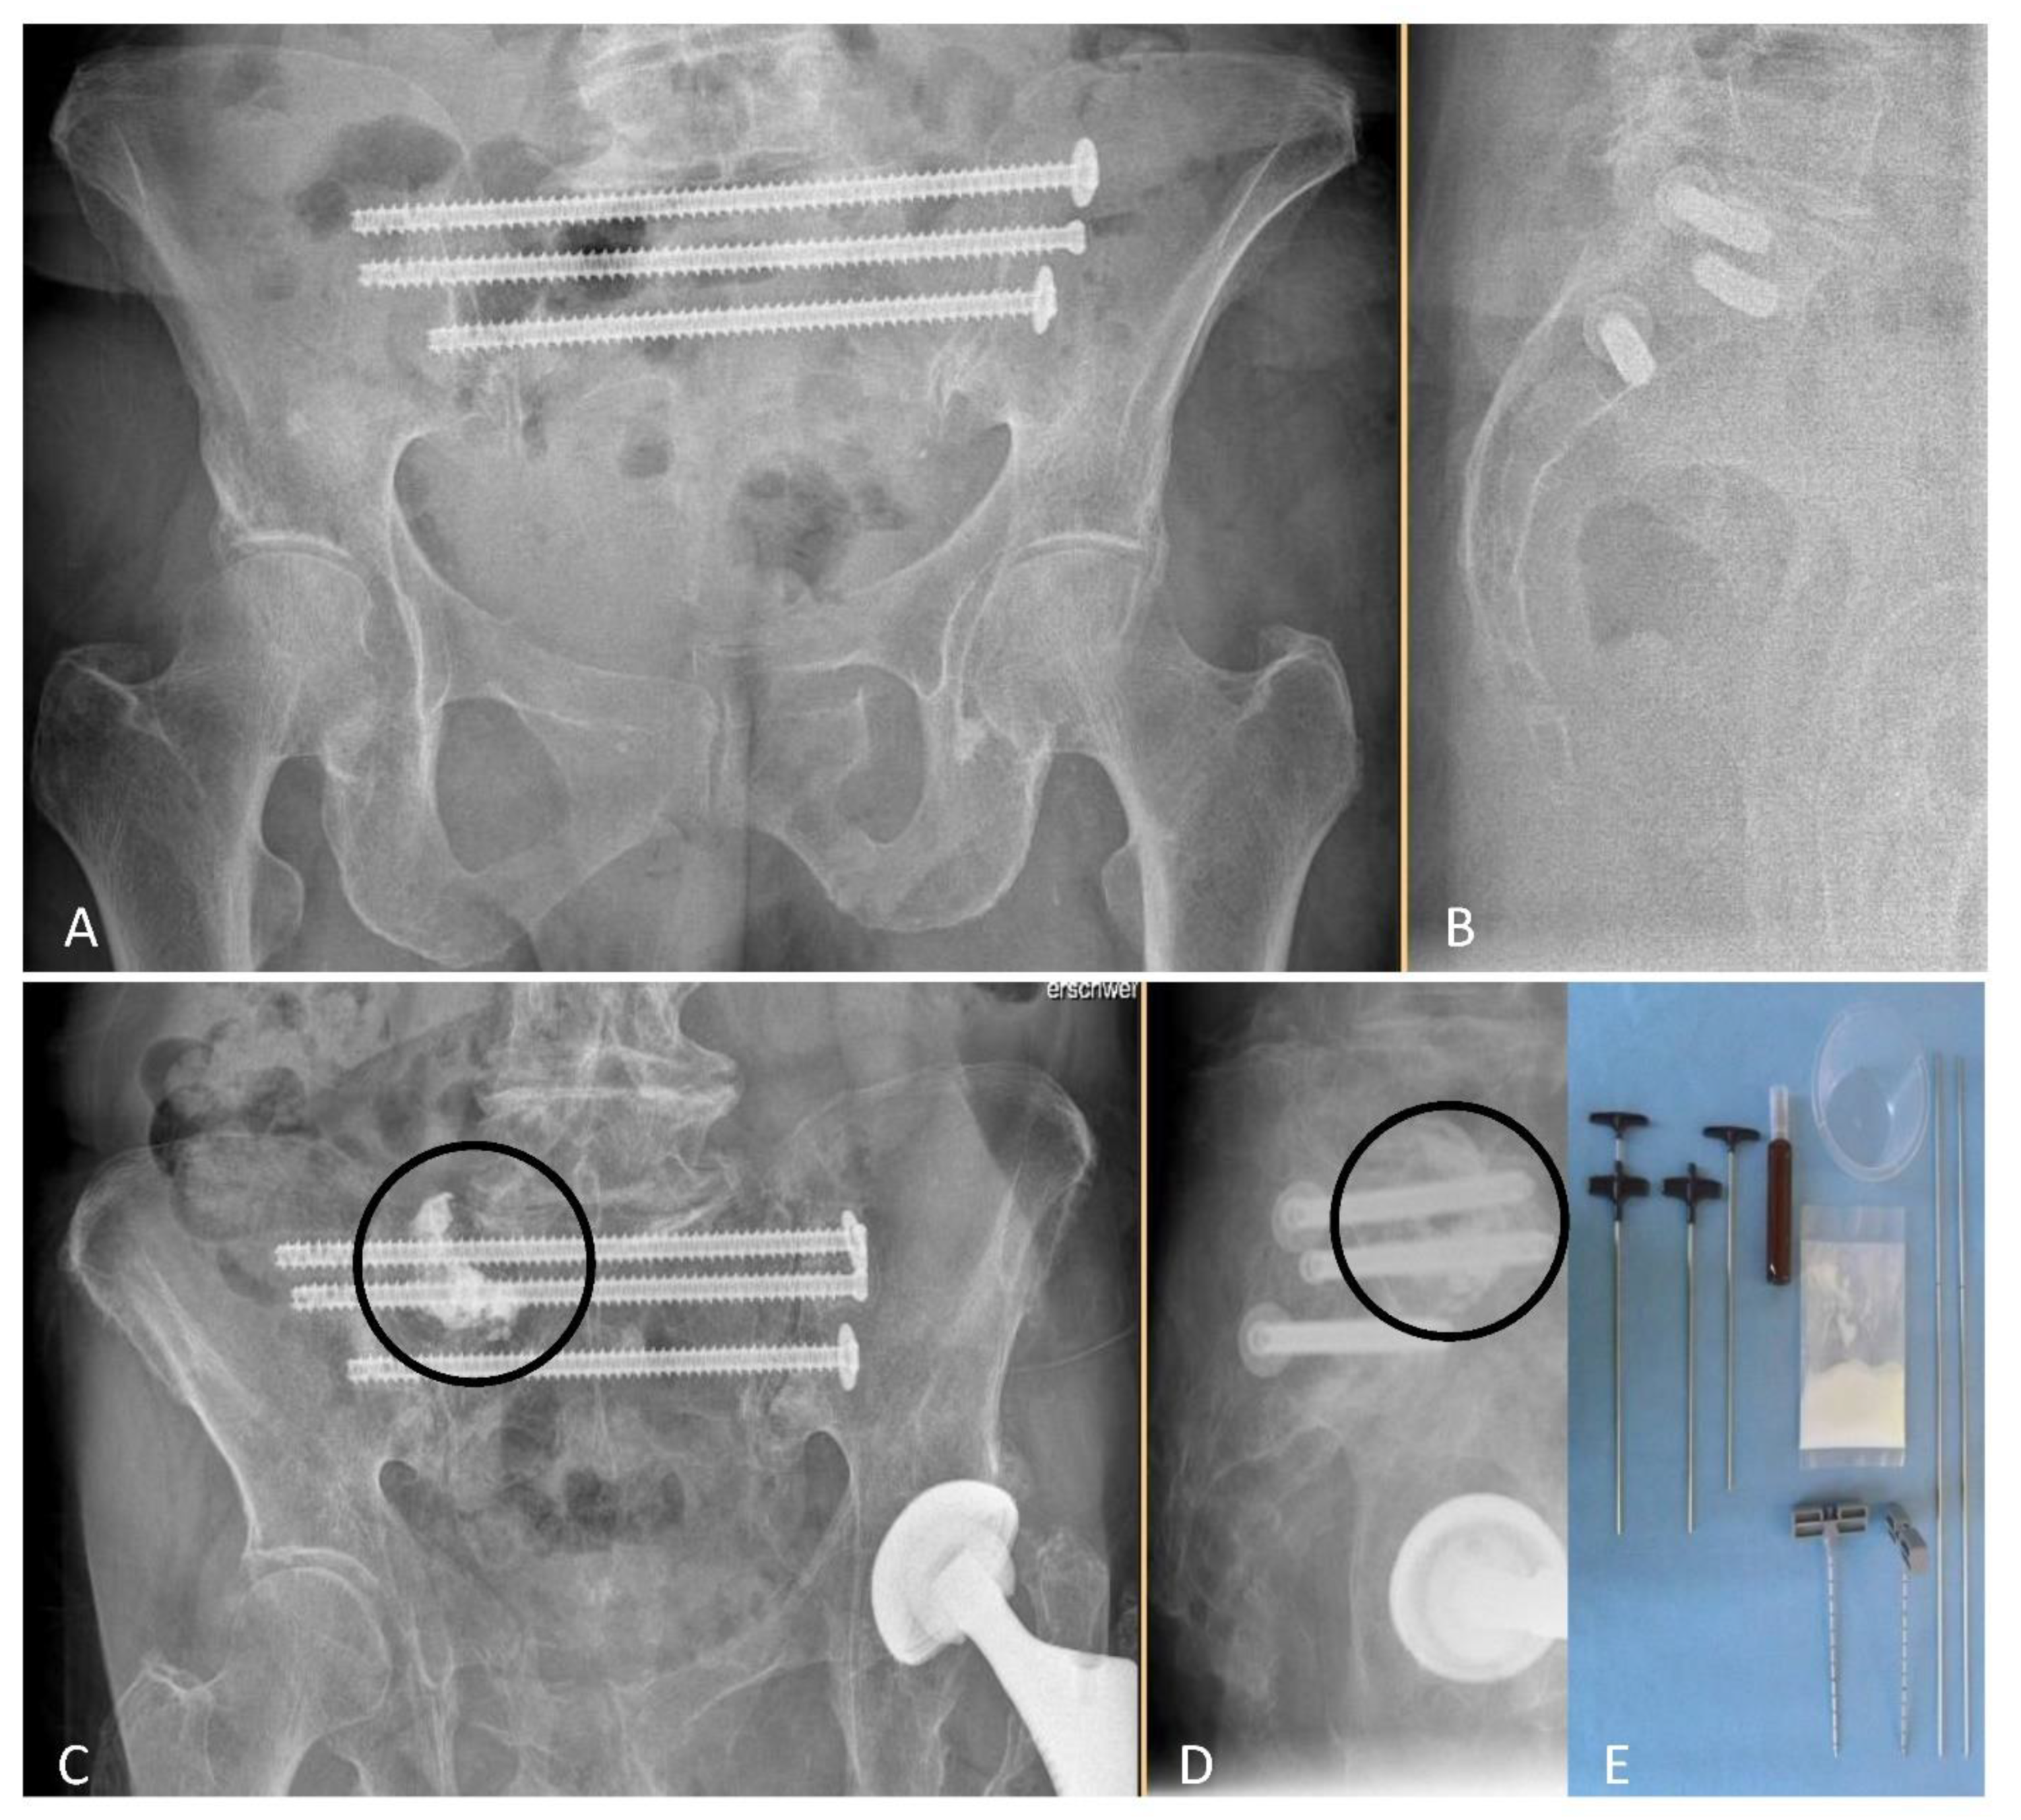

From October 2011 to May 2017, 52 individuals with 124 non-displaced sacral fractures had undergone surgery in form of NSF or NSF + ASP (Figure 1) after allocation to study groups.

Figure 1. Post-surgical radiographs (anteroposterior (A,C) and lateral views (B,D) in standing position) after NSF (A,B), or NSF + ASP ((C,D), cement location indicated by circles). Required disposable materials for an ASP procedure are shown in (E). NSF indicates navigation-assisted screw fixation; ASP, additional sacroplasty.